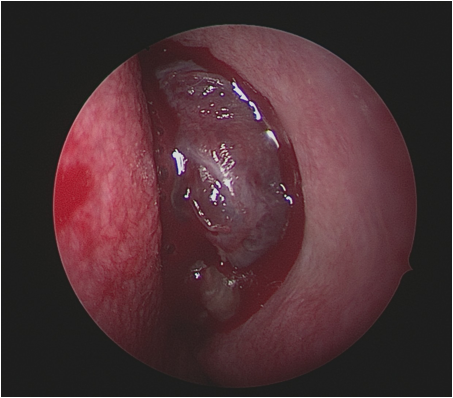

Las enfermedades de la base del cráneo requieren cirujanos expertos y procedimientos altamente específicos, considerando las dificultades anatómicas de la región y las importantes estructuras allí localizadas. En la Unidad Alergo·Rino tenemos una dilatada experiencia en el tratamiento de enfermedades tumorales y malformaciones que afectan a la base del cráneo. Somos expertos en el abordaje endoscópico mínimamente invasivo.

La Unidad dispone de un sistema de Navegación con imágenes de alta definición que aporta datos anatómicos en tres dimensiones para mejorar la orientación dentro del campo quirúrgico ayudando en los distintos pasos quirúrgicos y mejorando la seguridad. En nuestra Unidad tratamos todas las lesiones que afectan la base de cráneo tales como: tumores malignos de senos paranasales, angiofibroma juvenil, adenomas hipofisarios, cordomas, meningiomas, quistes de Rathke, y lesiones de la unión craneo-vertebral.